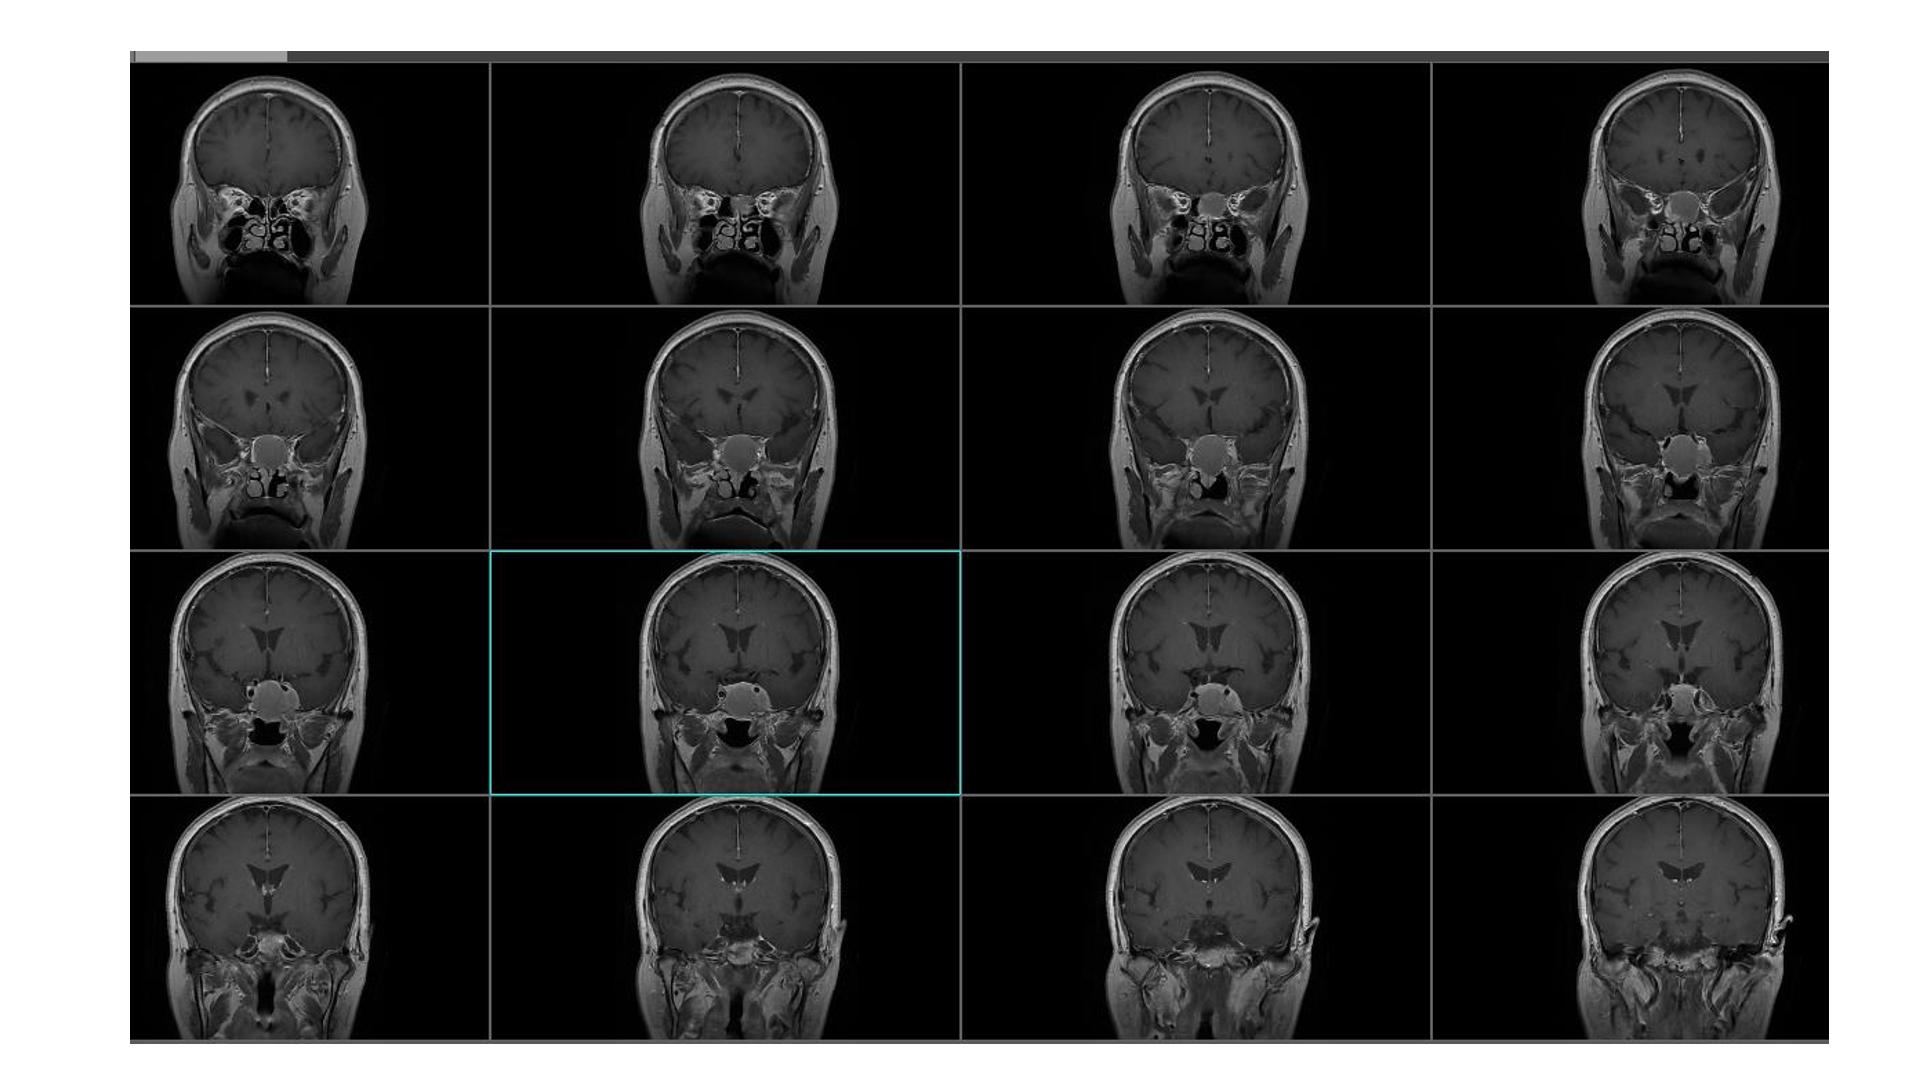

鞍区占位,蝶鞍扩大明显,侵袭海绵窦。